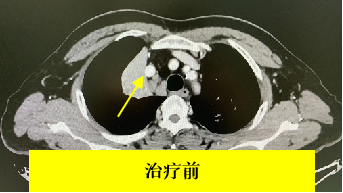

据其胸部增强CT检查显示,老秦肺部肿瘤长得十分刁钻。肿瘤有拳头大小,侵犯肺动脉、右肺上叶支气管开口,离心脏非常近(图1)。同时,也印证了肿瘤已出现纵隔淋巴结转移的情况(图2)。

图1 图2